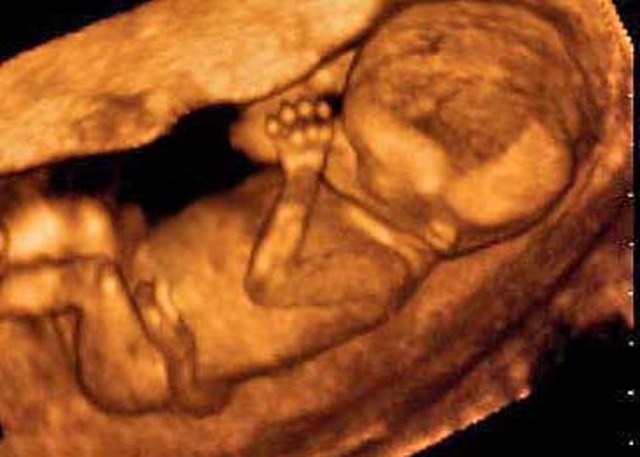

• Week 12

Week 12

The most dramatic development this week: reflexes. Your baby's fingers will soon begin to open and close, his toes will curl, his eye muscles will clench, and his mouth will make sucking movements. In fact, if you prod your abdomen, your baby will squirm in response. http://www.babycenter.com/6_your-pregnancy-12-weeks_1101.bc